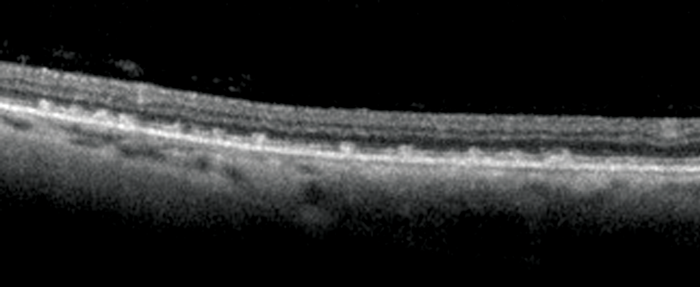

Figure 2: Left OCT of temporal retina.

1. What clinical sign is present in Figure 1a and b? What does the optical coherence tomography (OCT) in Figure 2 show and what clinical features can be seen in Figure 3?

1. Figures 1a and 1b exhibit Bitot spots. These are either dry or foamy greasy triangular excrescences of superficial intrapalpebral conjunctiva and represent keratinising epithelium. The foamy type is often associated with gas producing organism Corynebacterium xerosis. Figure 2 shows an OCT section with multiple excrescences at the level of the retinal pigment epithelium corresponding to the white dots seen in Figure 3. Figure 3 shows multiple, fine subretinal punctate white dots in the fundus. This is best seen in Figure 3b in which the white dots are seen contrasted against the background of a pigmented choroidal naevus. The dots can often resemble fundus albipunctatus.